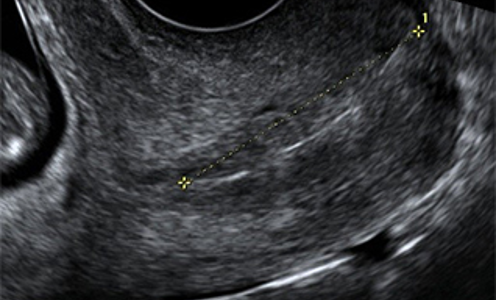

La Cervicometría, o ecografía para medición de la longitud cervical, se realiza por vía transvaginal. Consiste en la medición de la longitud del cuello del útero que es un indicador confiable del riesgo de parto prematuro. Su medición está indicada ante la presencia de contracciones uterinas y amenaza de parto antes del término.